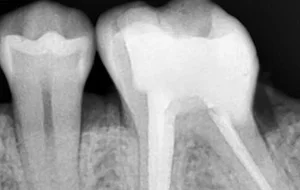

• This is followed by disinfection and shaping of pulp canals. The infected pulp is cleared out completely, canals are shaped and cleaned. Thorough disinfection is achieved.

• Clean and disinfected canals are then sealed and filled with an inert rubber-like filling material known as Gutta-Percha.

• The very last step is restoration & crown. The crown portion of the tooth cavity is then restored with a filling, followed by a Cap/Crown cementation.